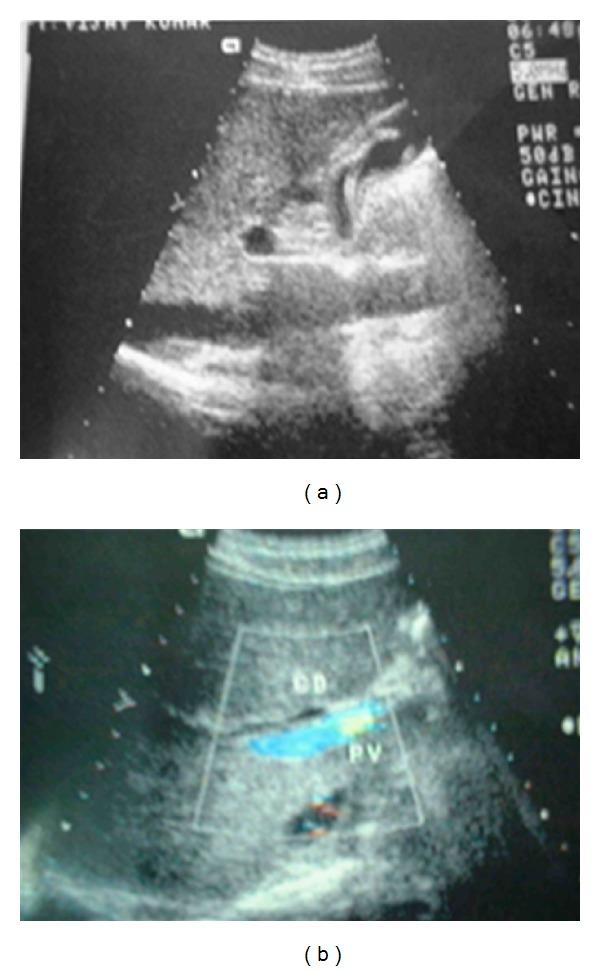

Ascariasis is one of the most common helminthic diseases in humans, occurring mostly in countries with low standards of public health and hygiene, thereby making ascariasis highly endemic in developing countries. In endemic areas, 30% of adults and 60-70% of children harbour the adult worm. Biliary ascariasis is a rare cause of obstructive jaundice. Conventional management involves endoscopic extraction of worm. We are reporting a rare case of ascaris which induced extrahepatic biliary obstruction in a young male who presented with acute cholangitis. The ascaris was removed by laparoscopic exploration of the common bile duct. Postoperative period was uneventful.

蛔虫病是人类最常见的蠕虫病之一,主要发生在公共卫生和卫生标准较低的国家,因此在发展中国家蛔虫病高度流行。在流行地区,30%的成年人和60%-70%的儿童体内有成虫。胆道蛔虫病是梗阻性黄疸的罕见病因。传统治疗方法是通过内镜取出蛔虫。我们报告了一例罕见的蛔虫病例,该病例导致一名患有急性胆管炎的年轻男性出现肝外胆管梗阻。通过腹腔镜探查胆总管取出了蛔虫。术后恢复顺利。